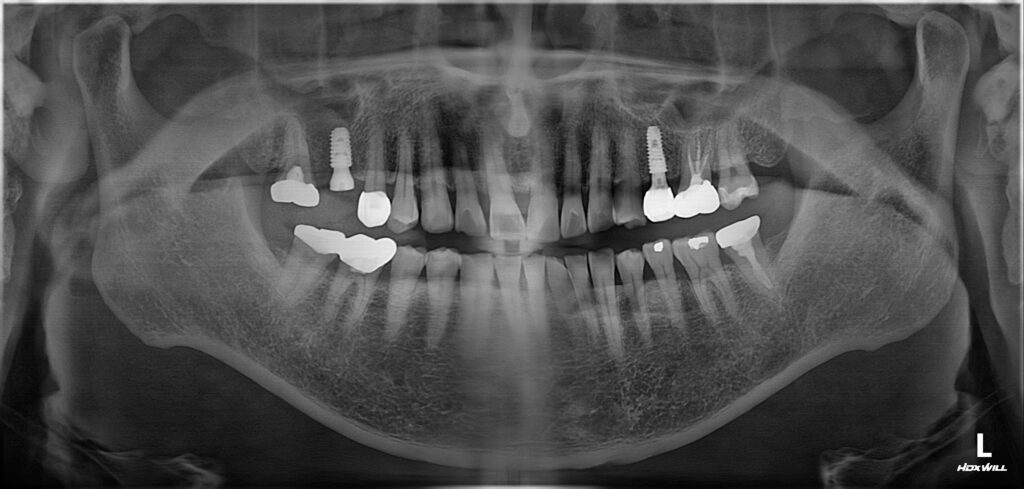

오늘은 광화문치과에서 뿌리까지 금이 간 치아를 발치한 뒤

즉시 임플란트를 식립하신 환자분을

소개해 드리도록 하겠습니다.

환자분께서는 발치를 하더라도

주변 뼈가 발달되어 있으셔서

치유가 좋을 것으로 예상하고

발치 3개월 후 임플란트 식립을

진행하도록 하였습니다.

초기 고정력은 15N정도로 강한편은

아니었기 때문에 다시 3개월정도

기다렸다가 보철 시행까지 마무리를 하였습니다.